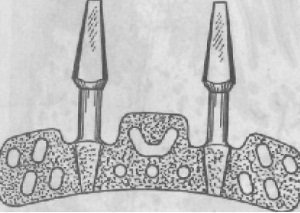

Ábra. 277. submucosalis implantátumok teljes fogsor felső állkapocs.

1. intramucosalis implantátumok (nyálkahártya alatti). Intramucosalis implantáció javítására használják rögzítéséhez protézis atrophia alveoláris csont a maxilla, különösen, ha hibák szájpad fejlődését. Az implantátum egy kétoldalas cap, amelyek közül az egyik mereven van rögzítve a bázis a lemez kivehető fogpótlás, a másik rész (gomba alakú) vezetünk be a létrehozott (anesztézia alatt) kerek fúróval lyukat a nyálkahártyában a felső állkapocs. Intramucosalis implantátumok titánból, egy erősen korrózióálló acélból, KHS. Általában két sor is - az egyik az alveoláris gerinc, a másik - a palatinális lejtőn, de nem több mint 14 (ábra 277.).